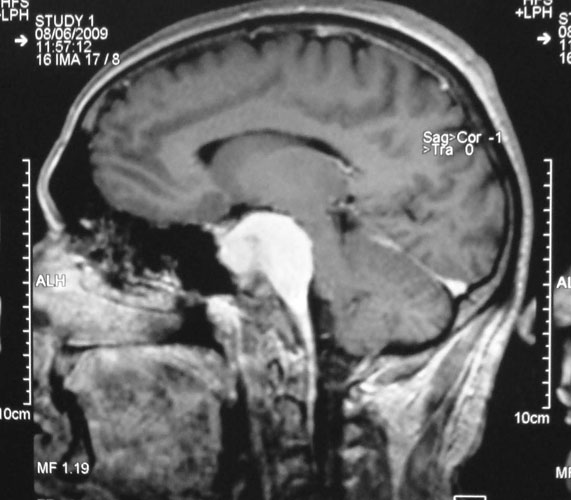

Pituitary Tumours

Pituitary is a small gland in the midline of skull base that has important role in maintaining hormonal milieu of the body. Tumors arising from pituitary present as gradually worsening partial blindness (‘field defects’), headache and endocrine abnormalities, commonest being acromegaly. Management involves a teamwork, with close association of neurosurgeon, endocrinologist and radiation oncologist. Surgery (through the nose or transcranial) is required to excise the tumor, followed by radiotherapy and management of hormonal deficiencies